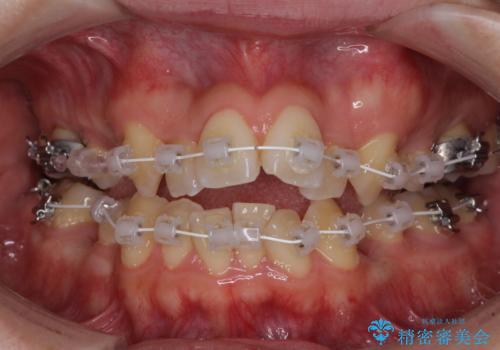

- 審美装置

- 2年6ヶ月

元の歯列が想像できないほど、きれいな歯列に整えることができました。

第二小臼歯抜歯の矯正治療は、治療期間が長引くことが多いですが、動きが非常に良く、予定の治療期間で終えることができました。